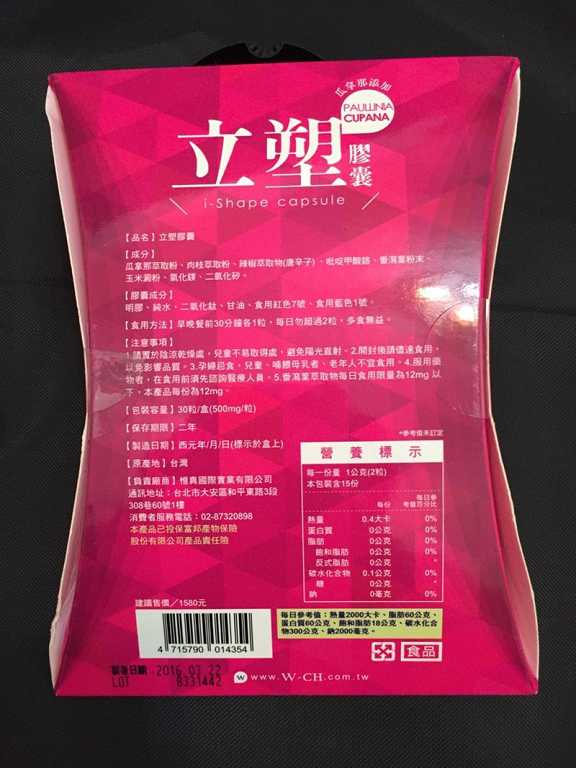

同時,謝謝【女人知己試用大隊】提供的–Supercut塑魔纖立塑膠囊

好啦,廢話不多說,就來試試繽紛小桃紅--Supercut塑魔纖立塑膠囊

每一盒Supercut塑魔纖立塑膠囊都有三小包,每一小包有10顆膠囊

Supercut塑魔纖立塑膠囊的成分有:瓜拿那萃取粉、肉桂萃取粉、辣椒萃取物(唐辛子)、吡啶甲酸鉻、番瀉葉粉末、玉米澱粉、氧化鎂、二氧化矽。

食用方式:早晚餐前30分鐘各1粒,每日不超過2粒。(多食無益)

包裝是桃紅色的

包裝是桃紅色的

番瀉葉萃取物每日食用限量為12mg以下,

番瀉葉萃取物每日食用限量為12mg以下,